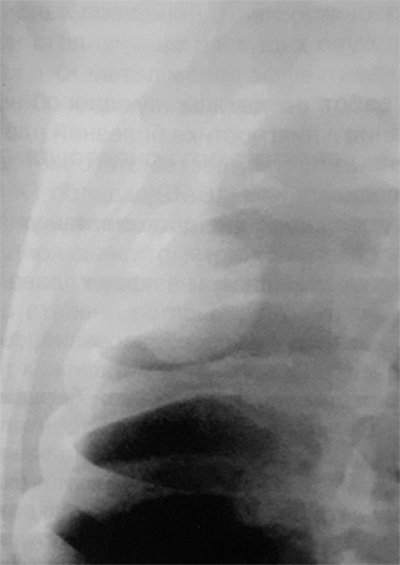

Рисунок 3. Доброкачественная плевральная фиброма. В нижнем отделе правого легочного поля визуализируется небольшое, четко ограниченное, однородное образование с несколькими дольчатыми контурами (см стрелка)

Рисунок 4. Фиброма плевры (доброкачественная опухоль). Увеличенный фрагмент рентгенограммы в прямой проекции – верхние отделы правого легочного поля. На снимке определяется образование округлой формы, которое широко прилегает к грудной стенке